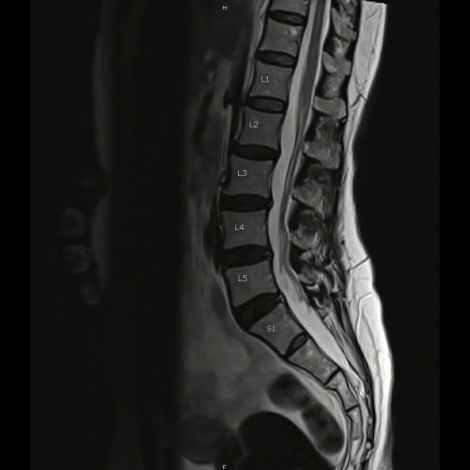

Lumbar Spine MRI

Your doctor may recommend an MRI to better diagnose or treat problems with your spine like injury-related pain, severe back ache, sciatica, infection, tumor, etc.